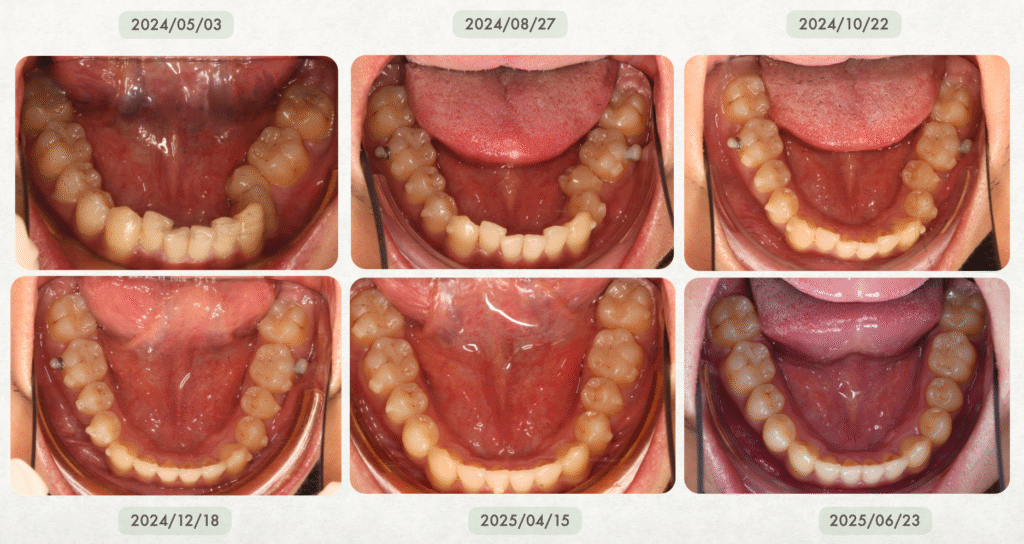

真實案例:隱適美有時甚至比傳統矯正還快!

在輕度到中度牙齒凌亂的案例中,隱適美不但不慢,反而更有效率、更快完成。

- 若配戴配合度良好,療程甚至可能在一年內順利完成

在 沐森美學牙醫 的實際經驗中,隱適美治療並不會特別久,甚至在某些案例中,反而可以比傳統矯正更有效率、完成得更快✨!

尤其在輕度到中等牙齒凌亂的情況下,隱適美有非常大的機會比傳統矯正更快速完成喔~而且費用也跟傳統矯正差不多!